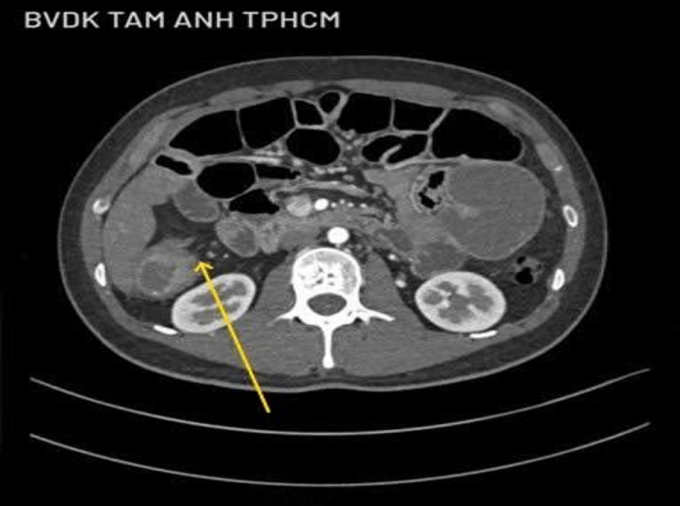

Anh Công ban đầu được chẩn đoán viêm dạ dày, ruột kích thích, điều trị bằng thuốc không đỡ, đến Phòng khám Đa khoa Tâm Anh Quận 7 chụp CT 100.000 lát cắt cho thấy đại tràng phải và các quai ruột giãn. Một đoạn ruột 5 cm mất cấu trúc, thâm nhiễm mỡ nhẹ xung quanh, nhiều hạch nhỏ xuất hiện quanh tổn thương. Ảnh nội soi cho thấy đại tràng góc gan có khối u sùi làm hẹp lòng, sinh thiết xác định ung thư đại tràng góc gan, tế bào ung thư xâm lấn sâu, rộng làm tắc ruột bệnh nhân.

Tiến sĩ, bác sĩ Đỗ Minh Hùng, Giám đốc Trung tâm Nội soi và Phẫu thuật Nội soi Tiêu hóa, Bệnh viện Đa khoa Tâm Anh, cho rằng anh Công phát hiện ung thư ở giai đoạn muộn nên khối u ở đại tràng ngang lớn gây tắc ruột, tế bào ung thư đã xâm lấn xuyên qua thành ruột đến bề mặt phúc mạc tạng, nghi ngờ di căn hạch bạch huyết.